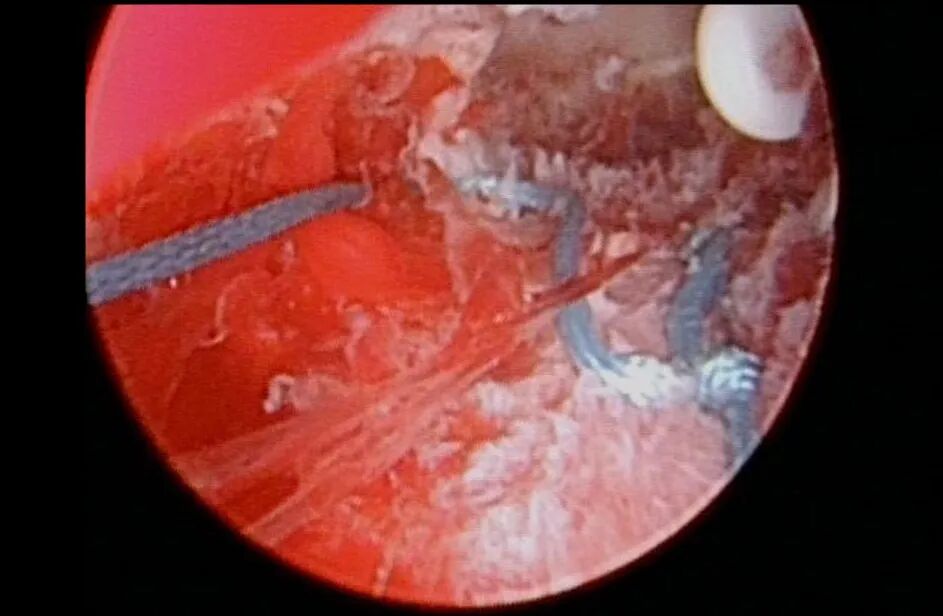

考虑到患者曼月乐环治疗腺肌症有效,病灶比较局限,拟行子宫腺肌症病灶射频消融+曼月乐环缝合固定术。